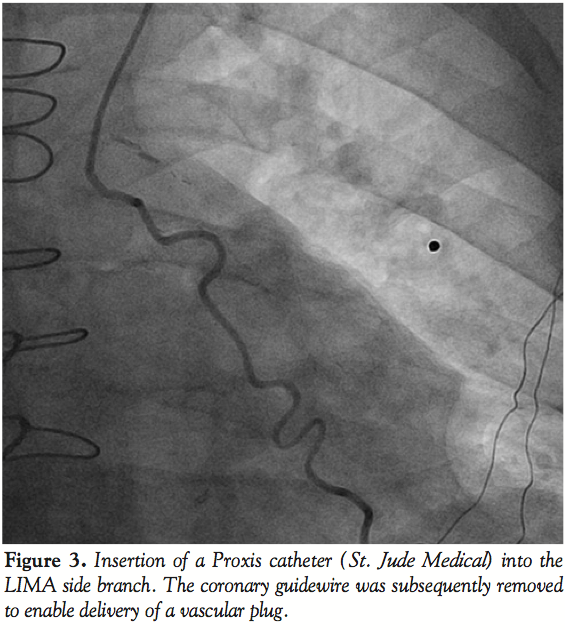

Left radial access was obtained with a 6 Fr sheath. The LIMA was wired with an Ironman wire (Abbott Vascular; Figure 2) and a Proxis catheter (St. Jude Medical) was inserted into the LIMA side branch (Figure 3). We attempted to deliver a 3 mm Amplatzer vascular plug (AGA Medical) through the Proxis catheter in the LIMA side branch, however significant resistance was encountered during delivery attempts. The device was partially deployed but in suboptimal location due to movement of the catheter during delivery. The vascular plug was recaptured and removed. LIMA angiography demonstrated side-branch occlusion. The LIMA side branch remained occluded after 15 minutes of observation. The patient had an uneventful recovery and has had no recurrent angina during 3 months of follow-up.